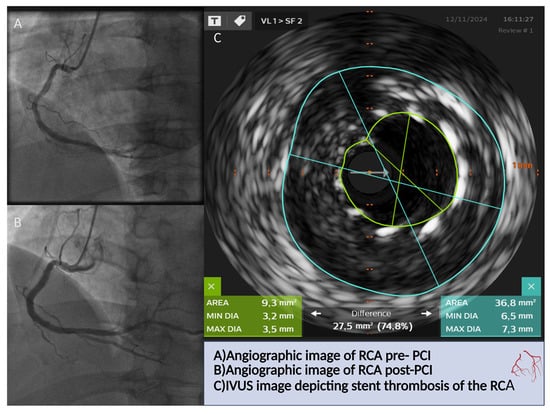

7.1. IVUS Versus FFR